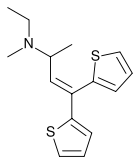

Thiambutenes

Structures